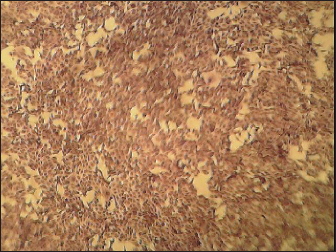

Noninfected BHK21 cell line (Fig. 6) showed normal cell shape and normal growth behavior while the RABV (obtained from infected mice brain) cytopathic effect (CPE) in mice demonstrated BHK21 cell line inoculated with the prepared brain suspension of nine infected showed specific CPE of RABV by the second day postinfection distinguished by rounding of cells followed by lysis in the cell and separation from the culture surface (Fig. 7) within 4–7 days postcell infection.

Fig. 6. Normal BHK-21 cell line.

Fig. 7. RABV infected BHK-21 cell line showing cell rounding.

Infection of the BHK21 cell line showed 100% positivity of infected mice brain suspension resulting in specific CPE of RABV by the second day postinfection as cell rounding followed by cell lysis and detachment of the cell sheet. These results match what was described by Consales et al. (1990), Knezevic (2008), and Hassanzadeh et al. (2011), who found that RABV could be harvested from BHK cell culture with similar findings at around 48 hours of infection.